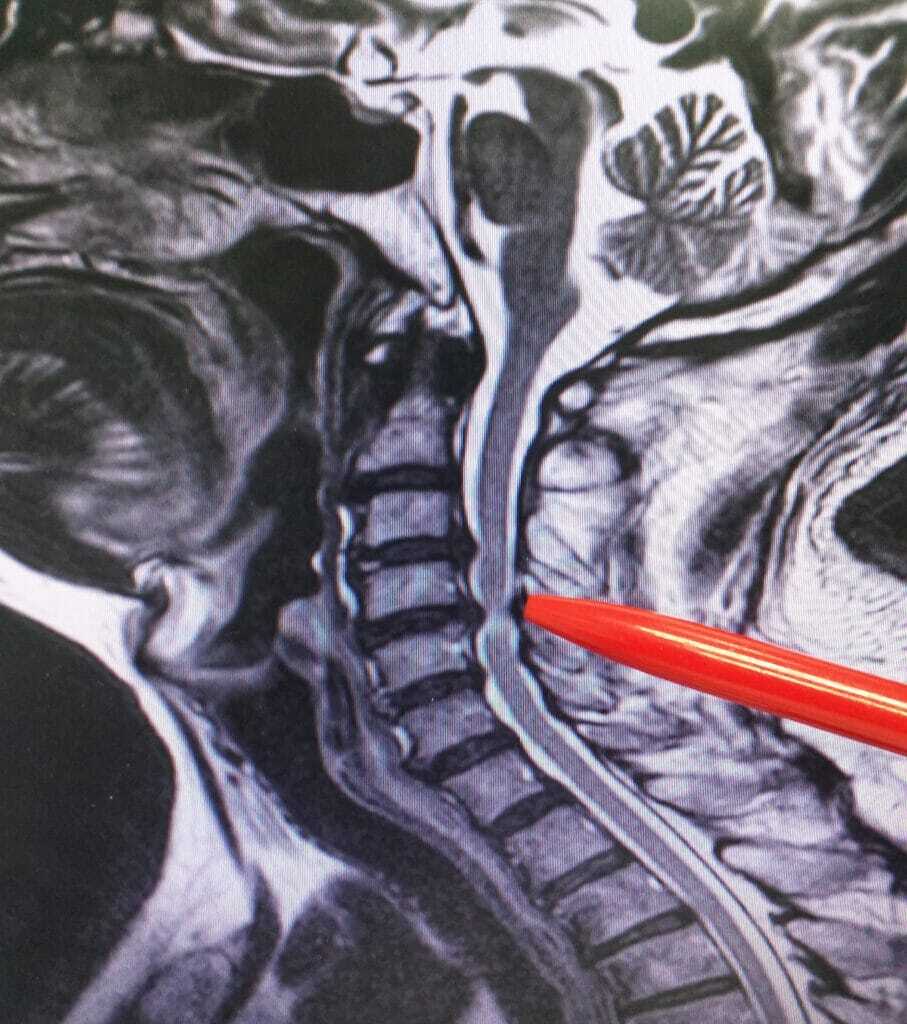

Patients may present themselves with numbness or pain radiating from the neck into the arm due to nerve compression. They may be diagnosed with cervical radiculopathy which is caused by herniated disc, or spondyliotic foraminal stenosis. When many doctors think there is a radiculopathy, a surgery will be recommended.

Chronic neck pain usually centers around the nerves. A disc in the neck can become herniated or “bulge” because of the wear and tear of the tendons, ligaments, and muscles. One possible diagnosis out of many may be spondylolisthesis – where one vertebra slides forward over the bone below it. Another reason neck pain is so prevalent is that the weight of the head is not proportionate to the strength and size of the neck, you do not have a good ability to hold your head up.

Of the many emails that I get are ones which discuss C1-C2 cervical spine instability. Many emails will talk about chronic upper cervical subluxation at C1-C2 and a reverse curve. The normal curve of the spine is shaped like a backwards “C.” If you have a problem with your neck, Lordosis is probably a word you are very familiar with. When your curve went from a natural “C” shape to a reverse curve you were probably told you had a reversed lordosis or your neck had become Kyphotic. Your neck is now curving in the opposite direction. This may be causing a lot of pain. Some of the pain maybe from muscle spasms. As the muscles are trying to stabilize the spine, the extra workload causes spasms.

When the spine is moving towards a reversed curve, adjacent segments may show cervical disc degeneration at lower levels such as C2-C3, C3-C4. These are the problems which will lead many people to a cervical spine fusion.